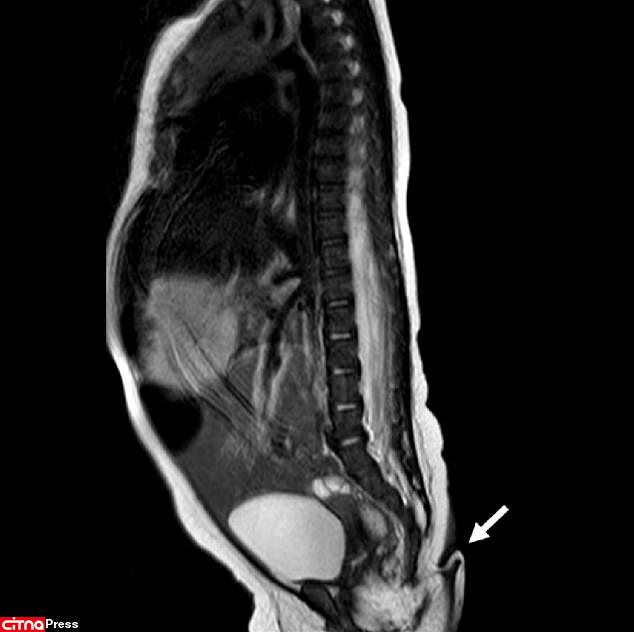

پزشکان می‌گویند این دختر مکزیکی از نظر سایر اندام‌ها از جمله مغز، قلب، کلیه و حس شنوایی سالم بود. همچنین، اسکن‌های پزشکی نشان داد که این دم نتیجه مشکلی در ستون مهره‌ها مثل دیسرافیسم نبود؛ این بیماری باعث می‌شود مهره‌ها به‌درستی شکل نگیرند و در پایین ستون آنها زائده‌ای شبیه دم رشد پیدا کند.

محققان پس از دو ماه دوباره این نوزاد را بررسی کردند و متوجه شدند که وزن و قد او در شرایط عادی قرار دارد. با این حال، اندازه دم 0.8 سانتی‌متر بزرگ‌تر شده بود. پزشکان درنهایت طی یک جراحی کوچک که با بی‌حسی موضعی انجام شد، این دم را قطع کردند. بررسی‌های بیشتر روی این زائده نشان داد که دم این کودک شامل بافت‌های نرم، رگ و مجموعه‌ای از اعصاب بوده است.